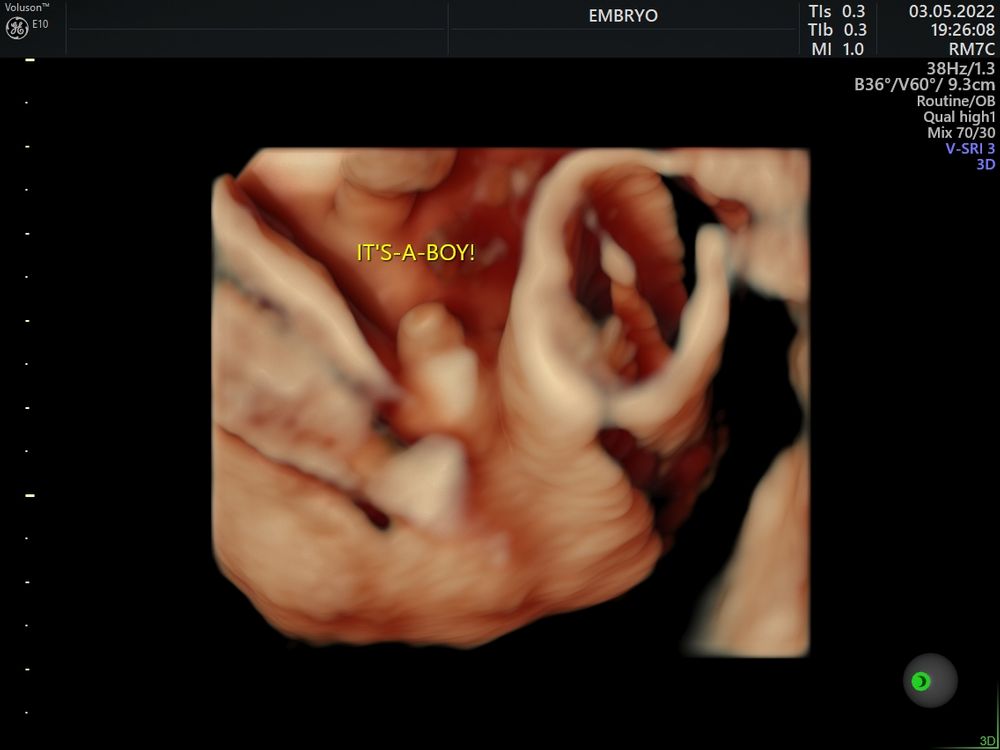

Пол малышаВсем привет, какова вероятность ошибки с полом на узи в 29 недель?

В 15, 17 и 21 - мальчик 100%

Яна, Вот и у меня все эти узи было очевидно что мальчик( фото прилагаю) , а сегодня ошарашили, думаю врач плохо посмотрела и все таки у нас пацан

JT, да я и сдала, по моему, на 15 неделе. Показало девочку, а потом 3 узиста на разных неделях и скрининге сказали мальчик и показали писюн)) сегодня опять вроде девочка, и кому верить не знаю)